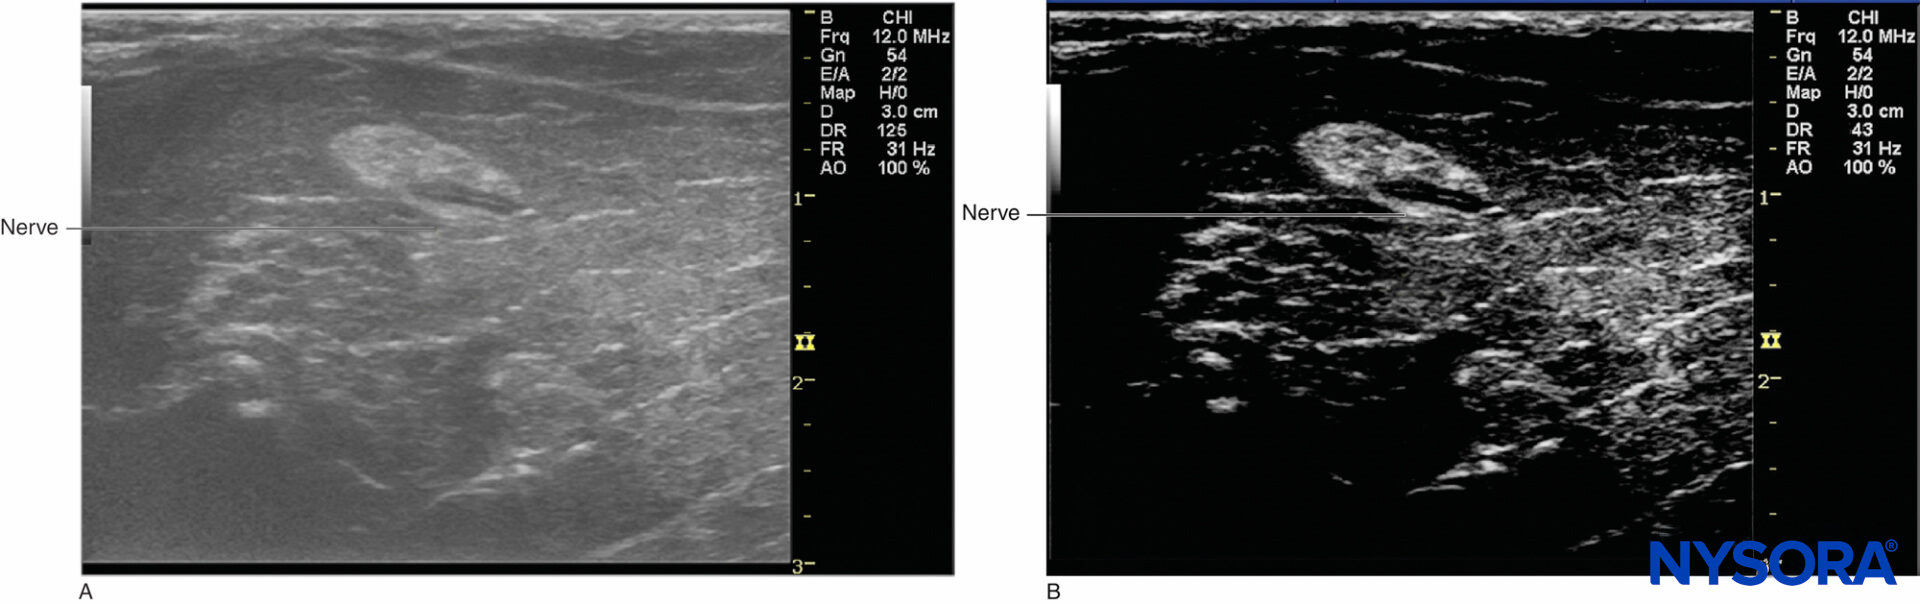

In 1880, French physicists Pierre Curie and his elder brother, Paul-Jacques Curie, discovered the piezoelectric effect in certain crystals. Paul Langevin, a student of Pierre Curie, developed piezoelectric materials, which can generate and receive mechanical vibrations with high frequency (therefore ultrasound). During World War I, ultrasound was introduced in the navy as a means to detect enemy submarines. In the medical field, however, ultrasound was initially used for therapeutic rather than diagnostic purposes. In the late 1920s, Paul Langevin discovered that high-power ultrasound could generate heat in bone and disrupt animal tissues. As a result, throughout the early 1950s ultrasound was used to treat patients with Ménière disease, Parkinson disease, and rheumatic arthritis. Diagnostic applications of ultrasound began through the collaboration of physicians and sonar (sound navigation ranging) engineers. In 1942, Karl Dussik, a neuropsychiatrist, and his brother, Friederich Dussik, a physicist, described ultrasound as a medical diagnostic tool to visualize neoplastic tissues in the brain and the cerebral ventricles. However, limitations of ultrasound instrumentation at the time prevented further development of clinical applications until the mid-1960s. The real-time B-scanner was developed in 1965 and was first introduced in obstetrics. In 1976, the first ultrasound machines coupled with Doppler measurements were commercially available. With regard to regional anesthesia, as early as 1978, La Grange and his colleagues were the first anesthesiologists to publish a case series report of ultrasound application for peripheral nerve block. They simply used a Doppler transducer to locate the subclavian artery and performed supraclavicular brachial plexus block in 61 patients (Figures 1A and 1B). Reportedly, Doppler guidance led to a high block success rate (98%) and absence of complications such as pneumothorax, phrenic nerve palsy, hematoma, convulsion, recurrent laryngeal nerve block, and spinal anesthesia. In 1989, Ting and Sivagnanaratnam reported the use of B-mode ultrasonography to demonstrate the anatomy of the axilla and to observe the spread of local anesthetics during axillary brachial plexus block.

Figure 1. A: Early application of Doppler ultrasound by LaGrange to perform a supraclavicular brachial block. B: Relationship of the brachial plexus of nerves and the subclavian artery.